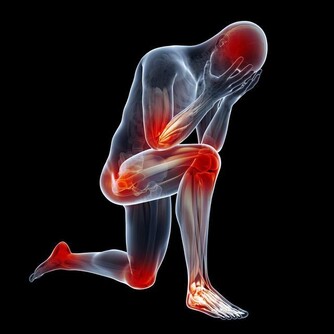

- 減少發炎反應:慢性發炎是癌症發生的主要因素之一,綠茶能減少體內發炎指數,降低癌變風險。